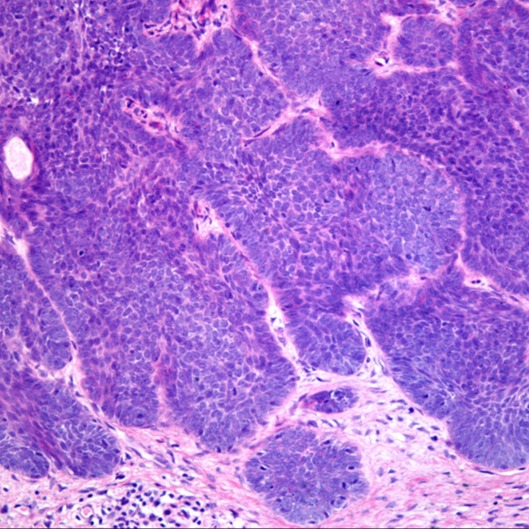

Se l’osservazione tramite dermatoscopio offre segni di sospetto, generalmente si fa ricorso a una biopsia cutanea, che consiste nel prelievo di una piccola parte di tessuto cutaneo lesionato da sottoporre a osservazione al microscopio. In questo modo è possibili distinguere correttamente le eventuali cellule tumorali presenti.